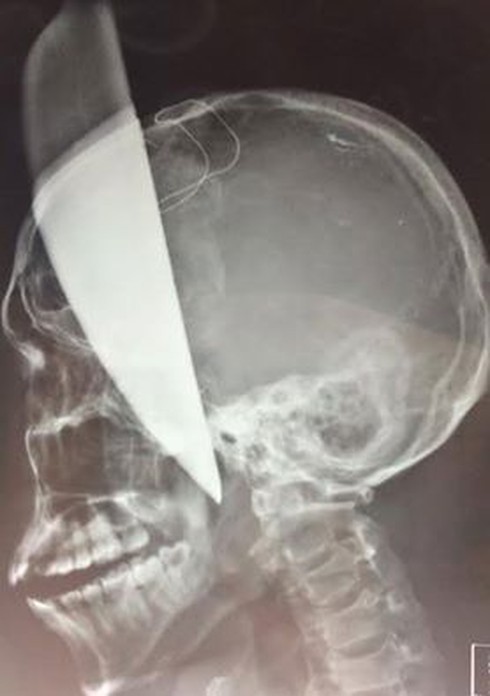

Hình ảnh dao bầu đâm vào đầu bệnh nhân quan phim chụp. |

Trước đó, rạng sáng ngày 18/8/2016, bệnh nhân này (25 tuổi, ở Nghệ An, làm công nhân tại Thanh Hóa) được các bác sĩ tuyến dưới của Thanh Hóa chuyển đến Bệnh viện Việt Đức trong tình trạng lơ mơ, mất máu nhiều và con dao bầu dài khoảng gần 40cm vẫn cắm trên đầu. Các bác sĩ đã nhanh chóng tiến hành hồi sức cho bệnh nhân và chụp hình ảnh con dao tại vị trí tổn thương. Kết quả cho thấy lưỡi dao cắm sâu vào vùng thái dương bên trái, xuyên hộp sọ, qua não, xuyên qua nền sọ xuống vùng hàm mặt của bệnh nhân.

Bác sĩ Nguyễn Đức Liên - khoa Phẫu thuật Thần kinh 2, Bệnh viện Việt Đức cho biết, ngay sau đó, bệnh nhân đã được chuyển vào phòng mổ. Do lưỡi dao nằm sát mạch máu lớn của não nên các bác sỹ phải dùng biện pháp mài vùng xương sọ quanh lưỡi dao để rút dao ra mà không làm đứt mạch máu não. Trong quá trình mổ, bệnh nhân bị mất 500 ml máu và phải cắt một số tổ chức não. Ca mổ kéo dài trong vòng 3 tiếng đã lấy được con dao bầu ra khỏi đầu nạn nhân.